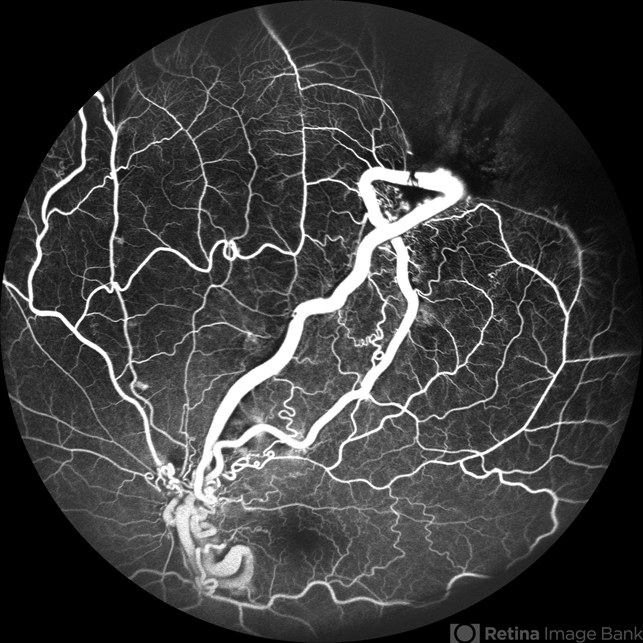

- racemose hemangioma, FFA in a case of Racemose angioma, arteriovenous malformation

- A case of 10 year old girl with defective vision in LE (6/60) who presented us with this condition.